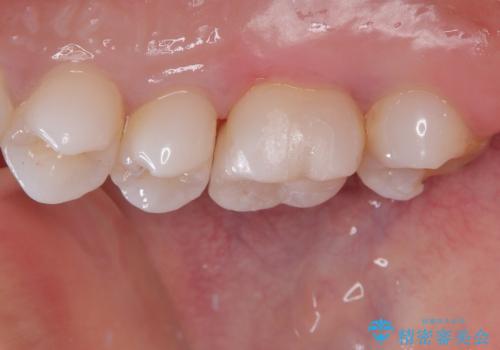

虫歯になってしまっているところをしっかりと除去し、形を整えて、精度の高いシリコーンによる型どりを行いました。

また、インレー接着時には唾液や血液による接着力の低下を防ぐためにラバーダム防湿を行っています。

精度の高い詰め物は二次的な齲蝕になりにくいです。